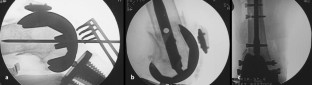

Abb. 5a–c